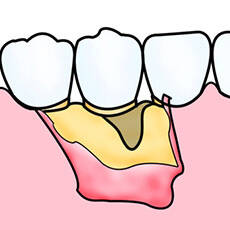

再生療法~

歯周病の進行により、歯を支えている骨は溶けてしまいます。通常、一度失った骨は元に戻りませんが、ケースによっては最新の再生療法によって歯周組織の回復が可能となりました。

①GTR法

歯周病によって失ってしまった歯周組織部位に、特殊な膜を挟み込むことによって歯周組織を再生させます。